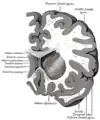

Section coronaire du cerveau immédiatement en face des ponts.

Section coronaire du cerveau à travers la masse intermédiaire du troisième ventricule.

Section coronaire du ventricule latéral et du troisième ventricule.

Section du cerveau montrant la surface supérieure du lobe temporal.